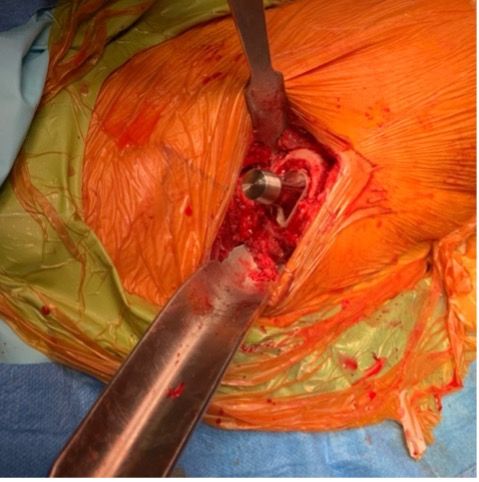

It seems clear that this type of implant lends itself well to minimally invasive approach routes due to the simplicity of preparing the femoral shaft and introducing the stem. Using the Hueter anterior approach without extensions to the orthopaedic surgery table, it is relatively straightforward to advance the compactors. Femoral preparation is simplified with no need for excess exposure of the proximal femur, with tension on the tensor fasciae latae muscle reduced through use of a femoral elevator. This is of course made easier by the curved design of the implant, but also by the orientation of the compactor along the femoral neck rather than following the diaphysis, as is the case with standard stems. On the contrary, irrespective of the approach route used, preserving as much femoral neck as possible can sometimes be awkward in the socket preparation stage.

Bone preservation is not the only advantage of this type of implant. Aggression to the soft tissues is also reduced. By the posterior route, the trajectory of the compactors is not restricted by any preservation of the piriformis tendon, and aligning the compactors with the curvature avoids any muscle damage caused by advancing instruments, especially in the gluteus medius. This also allows for soft tissue preservation and probably reduces post-operative limping.

Femoral neck cut -The femoral neck cut is made higher than for a straight stem since the stem will rest on the remaining neck segment to find its orientation. The optimal height and orientation are determined in the planning. Peri-operative fluoroscopy is relatively straightforward to carry out in the anterior approach in dorsal decubitus, and may be useful for a surgeon’s first few interventions, since there is always a tendency to cut too vertically and therefore too low, reducing support of the calcar. The femoral neck cut should be made even higher if the patient has a coxa vara morphotype.

Metaphyseal preparation - This starts by opening the femoral shaft using a specific curved rasp, which will guide the passage of the compactors of gradually increasing sizes. This preparation must be done as close as possible to the calcar. If the bone is very dense, a curette may be needed to prepare the calcar if the intention is to position a stem in a varus tilt or for the greater trochanter if a valgus position is the objective. This preparation should not be excessive since the principle of this implant is to compact the metaphyseal bone rather than to remove it. This step should preferably not be carried out before inserting the last compactor due to the risk of destabilising the final implant. If the surgeon is unsure, fluoroscopic guidance may be useful to confirm the positioning of the final compactor and to ensure that the plan has been followed and filling is correct. In any case this is what Loweg recommends. out cas ce que conseille Loweg [19].